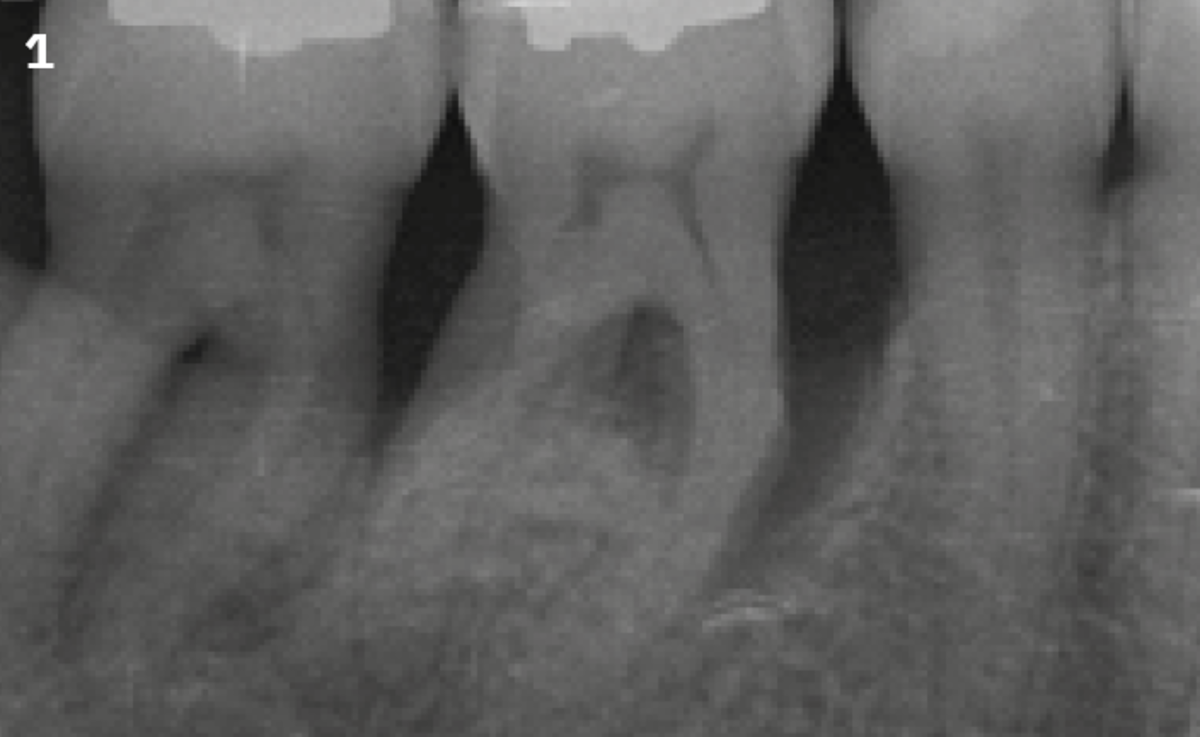

A patient with stage 3, grade C periodontitis was treated. After completion of non-surgical anti-infective therapy there was a residual deep infrabony pocket on tooth 46. Guided Tissue Regeneration with Geistlich Bio-Oss® and REGENFAST® was performed with an excellent outcome.